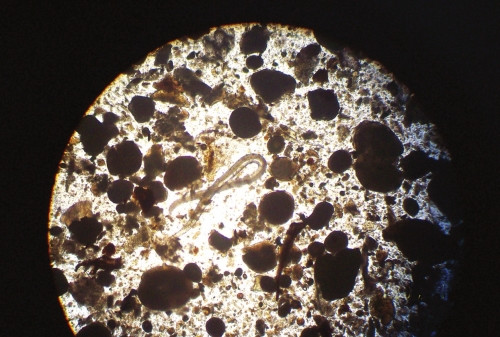

“通過DNA對(duì)比,這是條棘顎口線蟲。”昨日,川大寄生蟲學(xué)教授陳建平指著顯微鏡下的一條線狀蟲子說。這種名叫“棘顎口線蟲”的寄生蟲,是從泥鰍體內(nèi)找到的。

一天后,把被消化過的物質(zhì)過濾、沉淀、清洗后放到顯微鏡下,陳建平很快就找到一根只有200多微米的線狀蟲子。在顯微鏡下,這根線狀蟲子短粗,稍透明,兩端稍向腹面彎曲,前端為球形,上有8圈小鉤,頸部狹

窄,體前半部和近尾端處有很多體棘。陳建平說,這種蟲名叫棘顎口線蟲,寄生于魚、泥鰍、黃鱔體內(nèi),一條泥鰍體內(nèi)數(shù)量最多可達(dá)77條。